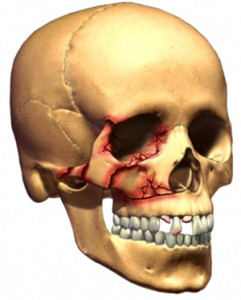

Изолированными подобные переломы бывают очень редко. Обычно это сочетание переломов лобной, височной, скуловой, верхнечелюстной и костной основой части носа. Они есть частью стенок глазницы. Соответственно, в случае перелома, например, левой скуловой кости, необходимо исследовать орбиту на наличие или отсутствие ее повреждения. Кроме того, при переломе каждой кости черепа наличие сотрясения головного мозга бывает практически всегда. Что касается изолированного перелома орбиты, то он составляет 16,1 % травм области лица. Такой перелом — результат прямого удара в область глазного яблока. Чаще всего это происходит с нижней и медиальной стенкой костей глазницы. Именно они ограничивают ее от околоносовых пазух, при этом имеют очень тонкую костную стенку. Этот вид травмы получил название «взрывной» или «blowout».

Нижняя стенка глазницы очень редко бывает повреждена изолированно. В большинстве случаев это происходит совместно с переломами верхнечелюстной кости, внутренней или наружной стенок глазницы.